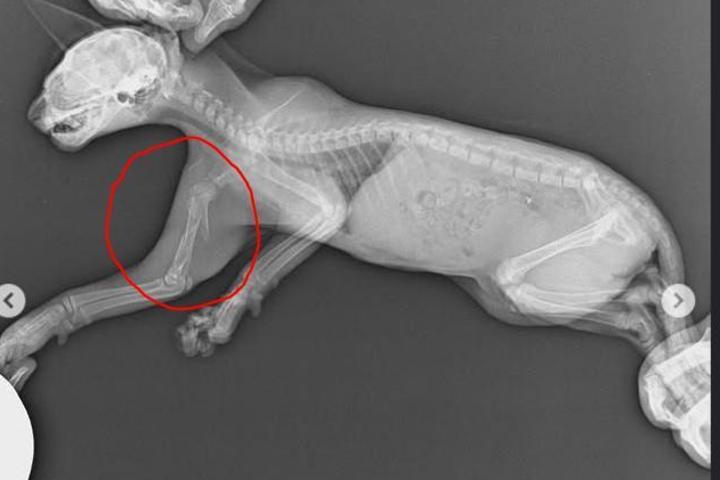

Urgente: Ayuda gatete atropellado

Ayer recibimos un aviso de un gatete que había sido atropellado en la calle Delicias (Madrid). Estaba solito, en medio de los coches… Lo rescatamos de inmediato y lo llevamos al veterinario de Mascoteros en Rivas Vaciamadrid, donde confirmaron que tiene roto el húmero.

Ahora se encuentra en nuestro refugio, tomando antiinflamatorios y con todos nuestros cuidados ❤️. Mañana volverá al veterinario para que el traumatólogo valore si puede ser operado.

Necesitamos de vuestra ayuda para que este pequeñín tenga la oportunidad de ser operado y disfrutar de un hogar feliz ✨.

Nuestra pequeñita ayer pasó por una operación de húmero. Ahora está adolorida, pero con muchísima fuerza y valentía ✨. Confiamos en que pronto se recupere y pueda comenzar una nueva vida, llena de amor y cariño en el calor de un hogar .